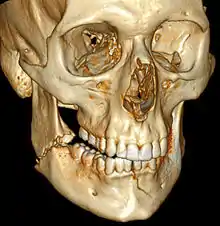

| 3D computed tomographic image of a mandible fracture in two places. One is a displaced right angle fracture and the other is a left parasymphyseal fracture. | |

Computed tomography is the most sensitive and specific of the imaging techniques. The facial bones can be visualized as slices through the skeletal in either the axial, coronal or sagittal planes. Images can be reconstructed into a 3-dimensional view, to give a better sense of the displacement of various fragments. 3D reconstruction, however, can mask smaller fractures owing to volume averaging, scatter artifact and surrounding structures simply blocking the view of underlying areas.